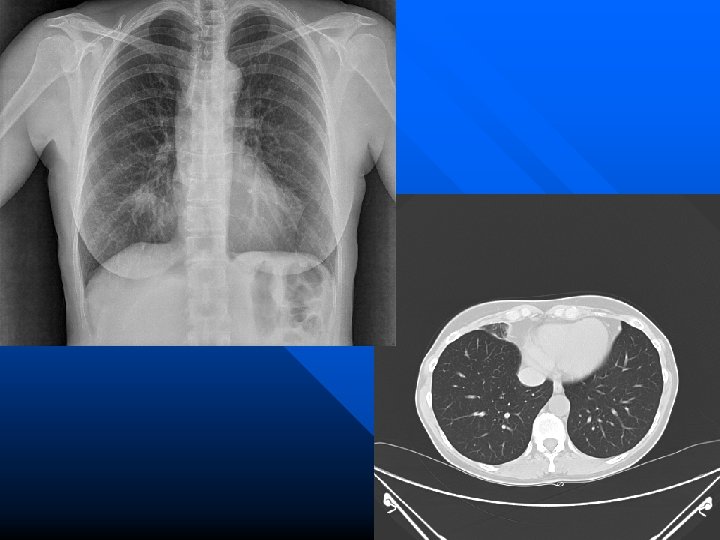

Quadri Broncografici di bronchiectasie

Immagini T A C di bronchiectasie